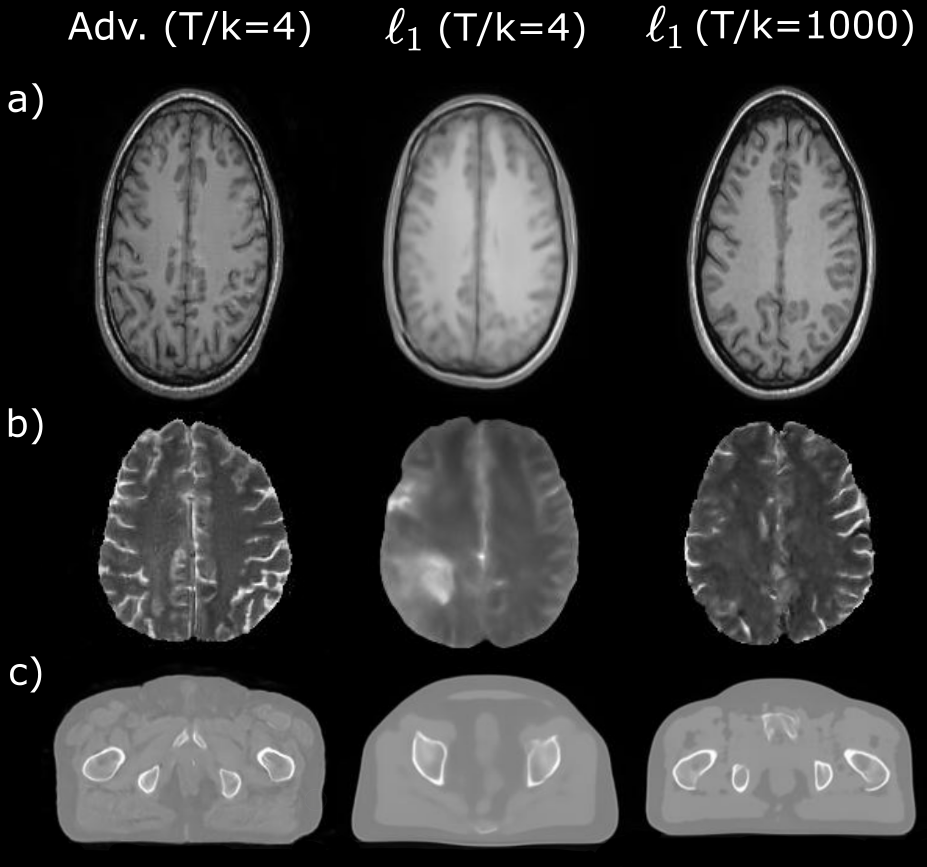

We conducted a set of ablation studies to systematically evaluate the importance of the main elements in SynDiff. To demonstrate the importance of the adversarial diffusion process, we compared the diffusive module in SynDiff based on an adversarial projector against a variant diffusive module based on an -loss based projector for reverse diffusion. The variant module shared the same overall loss function, albeit it ablated the adversarial loss terms for the diffusive generators and discriminators. As such, the remaining loss terms for the diffusive module were based on pixel-wise -loss similar to regular diffusion models. For focused assessment of the diffusive module, demonstrations were performed in unconditional synthesis tasks where guidance from the non-diffusive module was removed from all models. Synthetic images in representative tasks are displayed in Fig. 6, and FID scores are listed in Table 6. Compared to the projector at =4, the adversarial projector at =4 substantially improves visual image quality and FID scores over the projector at =4, while performing competitively with the projector at =1000. These results demonstrate the utility of adversarial projections for efficient and accurate image sampling during reverse diffusion.